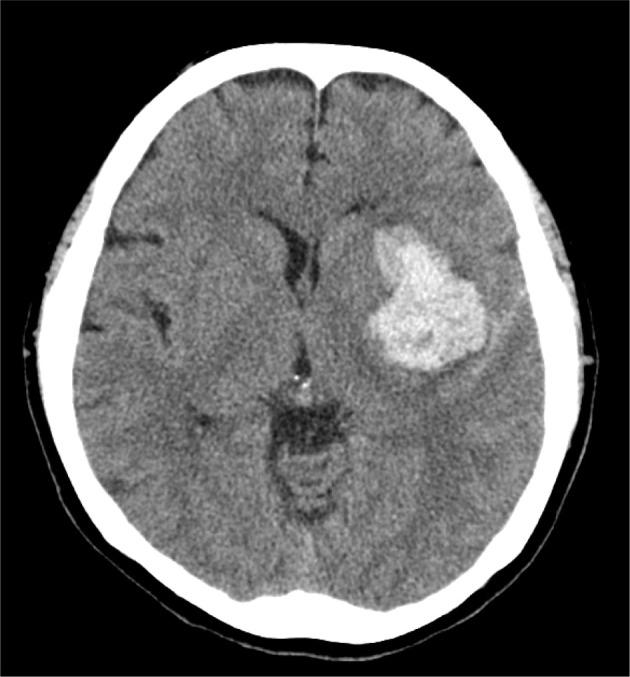

[Purpose] This study aimed to examine the effect of body weight-supported overground training on gait recovery in a patient with severe stroke-induced hemiplegia. [Participants and Methods] The participant was a woman in her 40s with severe hemiplegia following a stroke. A single-case ABAB design was employed. Standard physiotherapy was provided in the first and third phases, while physiotherapy combined with body weight-supported overground training was administered in the second and fourth phases. Walking speed, Timed Up and Go test, Brunnstrom recovery stage (BRS) and Fugl-Meyer Assessment (FMA) for motor function, and motor-functional independence measure (m-FIM) for activities of daily living (ADL) were performed to assess efficacy of body-weight-supported overground training. [Results] Walking speed improved from 0.26 m/s at admission to 0.37 m/s in the first phase, 0.58 m/s in the second phase, 0.45 m/s in the third phase, and 0.50 m/s in the fourth phase, reaching 0.40 m/s with a T-cane at discharge. m-FIM scores increased steadily from 20 points at admission to 74 points at discharge, while BRS and FMA showed minimal improvement. [Conclusion] Body weight-supported overground training may enhance walking ability, functional performance, and ADL independence in patients with severe stroke-induced hemiplegia.

[目的] 本研究旨在探讨减重地面训练对重度脑卒中偏瘫患者步态恢复的影响。[参与者与方法] 参与者为一名40多岁的女性,因脑卒中导致严重偏瘫。采用单病例ABAB设计。在第一阶段和第三阶段提供标准物理治疗,而在第二阶段和第四阶段实施物理治疗结合减重地面训练。通过步行速度、计时起立行走测试、Brunnstrom恢复阶段(BRS)和运动功能Fugl-Meyer评估(FMA)以及日常生活活动(ADL)的运动功能独立性测量(m-FIM)来评估减重地面训练的疗效。[结果] 步行速度从入院时的0.26 m/s提高到第一阶段的0.37 m/s、第二阶段的0.58 m/s、第三阶段的0.45 m/s和第四阶段的0.50 m/s,出院时使用T形手杖的步行速度达到0.40 m/s。m-FIM评分从入院时的20分稳步提高到出院时的74分,而BRS和FMA的改善最小。[结论] 减重地面训练可能会提高重度脑卒中偏瘫患者的步行能力、功能表现和ADL独立性。